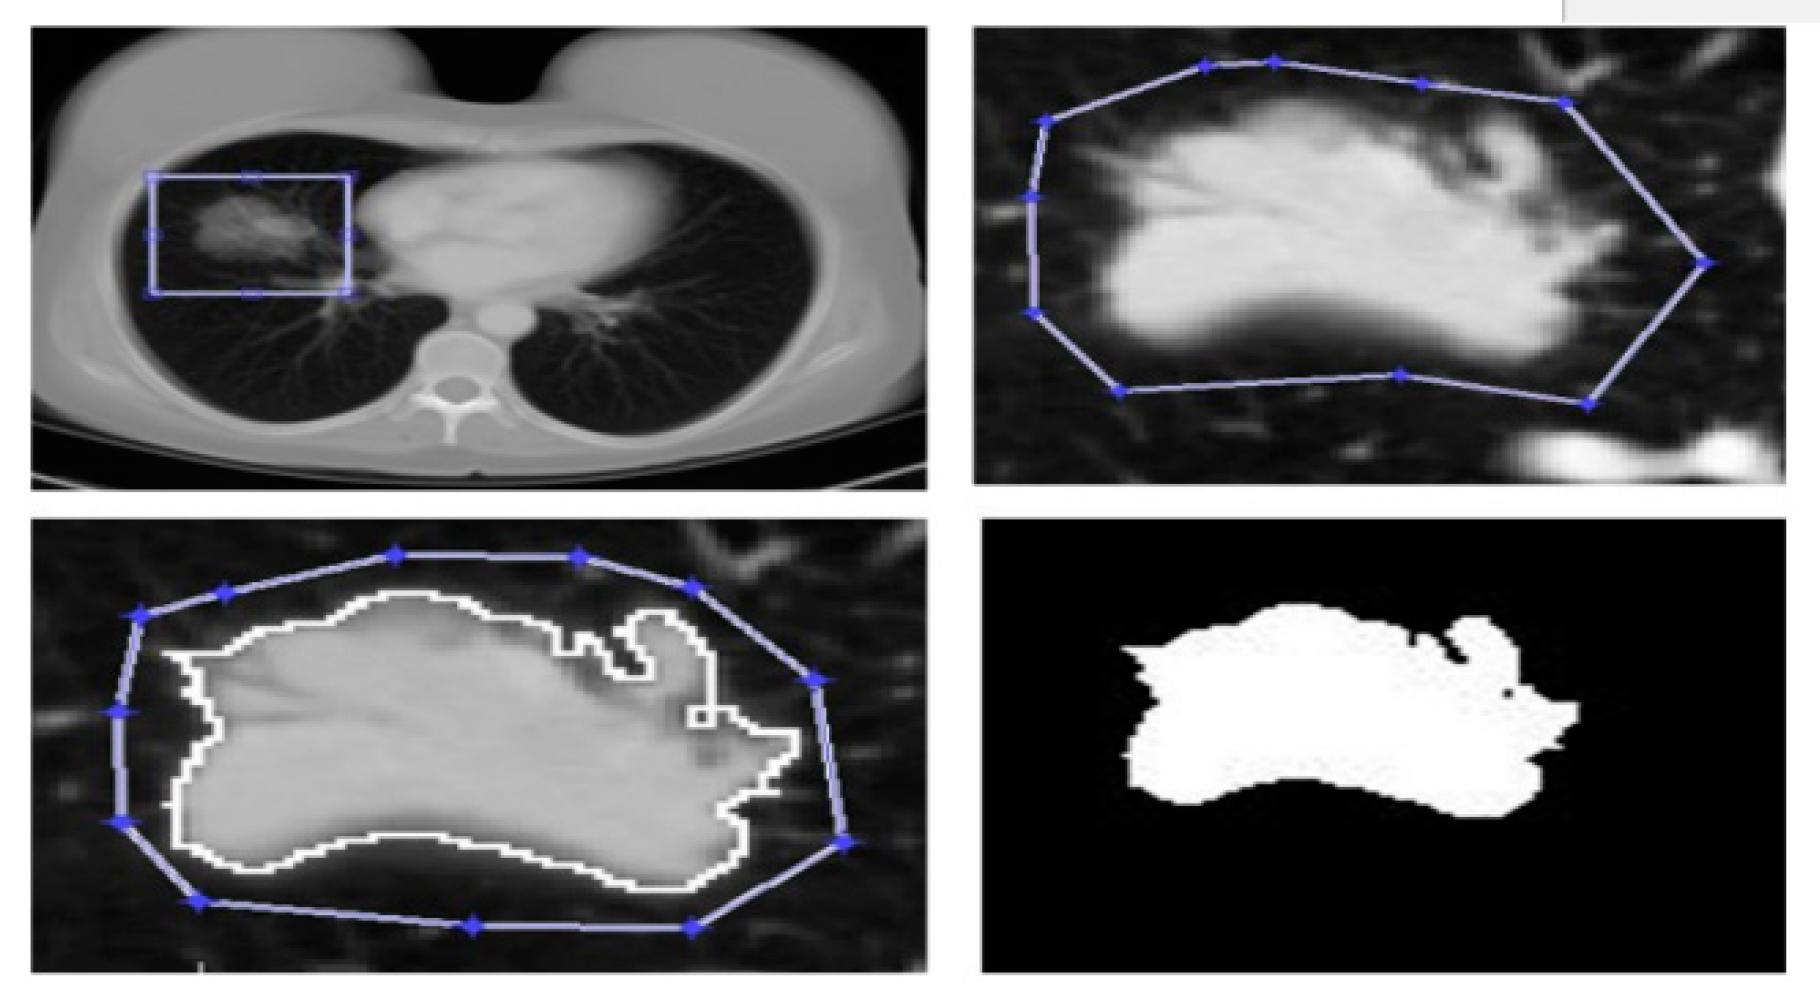

Use Of The Methods Of Segmentation C-Means, K-Means And Fractal Geometry In The Study In Alive Of the Cancer Of Lung (12).

- Rivero Borja, Mario Andres, and Jose Eduardo Escobar Martinez. “Uso de los métodos de segmentación c-means, k-means y geometría fractal en el estudio in vivo del cáncer de pulmón.” (2020).